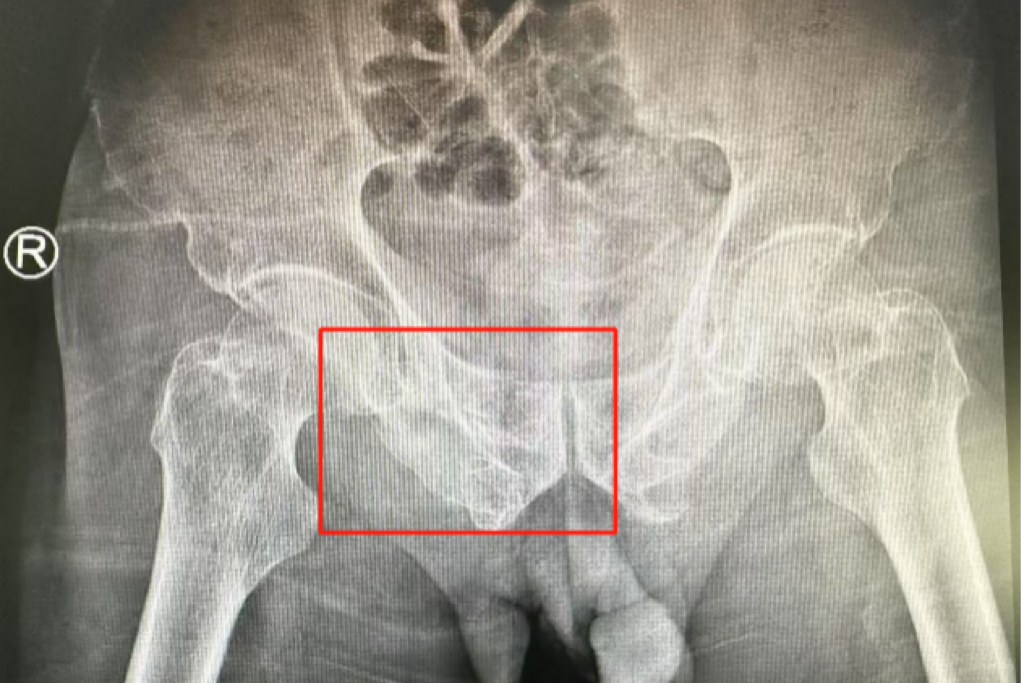

術前影像學顯示,患者的左側骶骨骨折,右側恥骨骨折、髂骨骨折,骨盆骨折分型為C型,老年脆性骨盆骨折分型為IV型,是極度不穩(wěn)定型的前環(huán)骨折和雙側后環(huán)骨折。所幸沒有明顯的骨盆出血或內臟損傷的表現(xiàn)。

術后第二天,醫(yī)生團隊復查X片顯示螺釘植入位置非常滿意,骨折基本達到穩(wěn)定復位,同時,復查的全血細胞計數(shù)中,血紅蛋白指數(shù)為102g/L。術后第三天,在智能骨科病房護理團隊及康復師的指導和護理下,王大爺可以坐立在床上。術后第四天,王大爺迎來了出院日,“得虧有了這么先進的醫(yī)療技術,讓我還能下地行走,謝謝你們!”

螺釘植入位置非常滿意

王大爺身體恢復良好